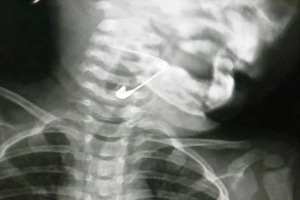

Kim băng dài 3 cm bung ra trong miệng thực quản bé trai

Lấy cây kim băng trong thực quản bé 18 tháng tuổi